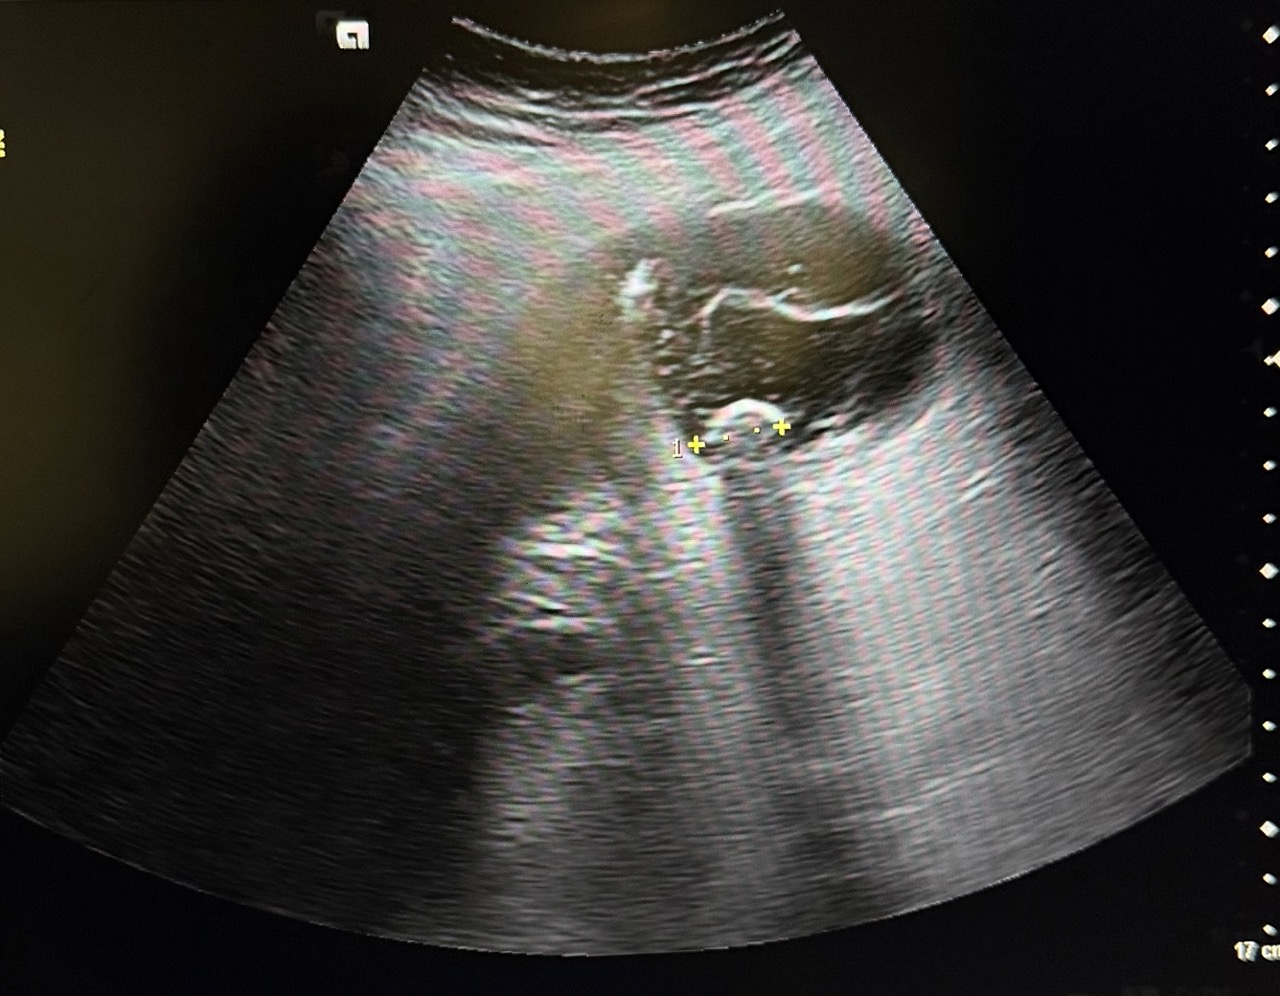

Ecografía en el centro de salud: Vesícula biliar con presencia de litiasis en su interior, distendida y engrosada. Murphy ecográfico positivo.

Desde el centro de salud, con la exploración y los hallazgos de ecografía nos orientó a colecistitis aguda litiásica por lo que se decidió traslado a urgencias para realización de analítica, ecografía por radiólogo y valoración por cirugía general.

La analítica junto con ecografía de urgencias coincidió con hallazgos observados en la ecografía del centro de salud, confirmando así colecistitis aguda evolucionada.